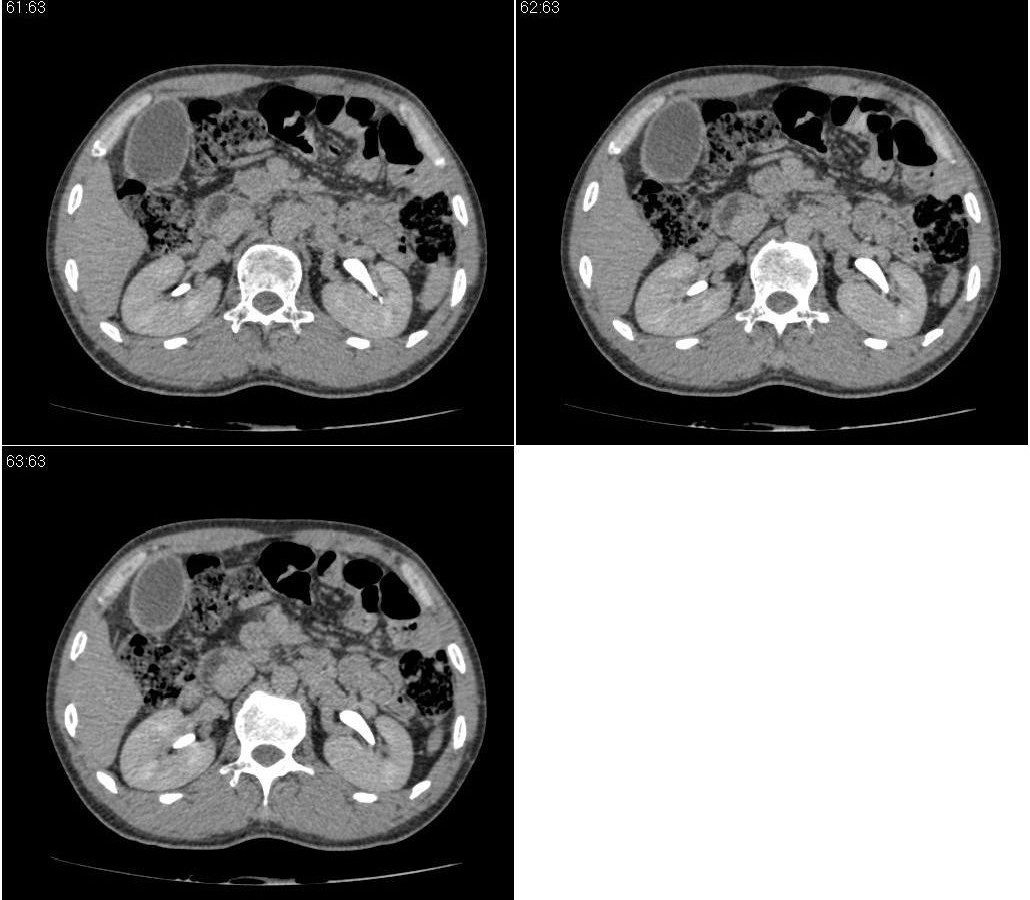

标题: CT21384:男性,50岁。发现无痛性黄疸十余天,B朝提示肝胆管 [打印本页]

标题: CT21384:男性,50岁。发现无痛性黄疸十余天,B朝提示肝胆管

1.考虑:壶腹占位病变(癌?)。

2.胆系低位梗阻:肝内外胆管扩张,胆囊增大,胰管扩张。

胆系低位梗阻:肝内外胆管扩张,胆囊增大,胰管扩.壶腹癌。

胆系低位梗阻(肝内外胆管扩张,胆囊增大,胰管扩张);考虑胰头癌或壶腹癌所致。

胆系低位梗阻(肝内外胆管扩张,胆囊增大,胰管扩张,钩突似有占位);考虑胰头癌